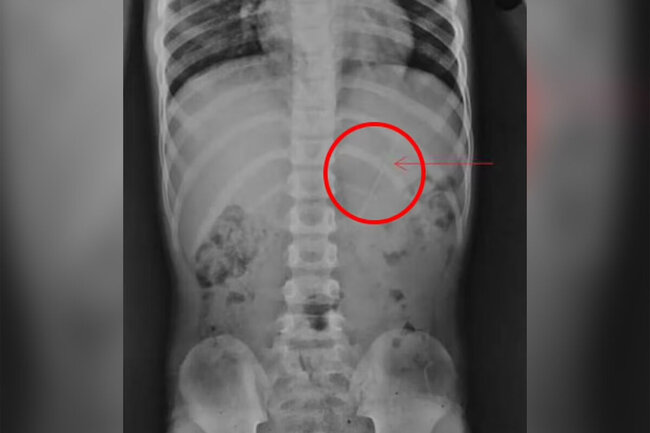

10 santimetrlik qələm udan uşaq sağ qaldıNepalda yeddi yaşlı uşaq təsadüfən 10 sm uzunluğunda qələm udub.

Bildirilib ki, ana yeddi yaşlı oğlunu Katmandu xəstəxanasına aparıb. O, uşağın qələmlə oynadığını və yanlışlıqla udduğunu bildirib.

Uşaq baş verənləri dörd saat sonra valideynlərinə danışıb.

Müayinə zamanı həkimlər mədədə yad cisim aşkar ediblər, balaca xəstə müşahidə altında qalıb və əməliyyata hazırlanıb.

Lakin bir gün sonra qələm həyati orqanlara zərər vermədən təbii şəkildə bədəndən çıxıb.